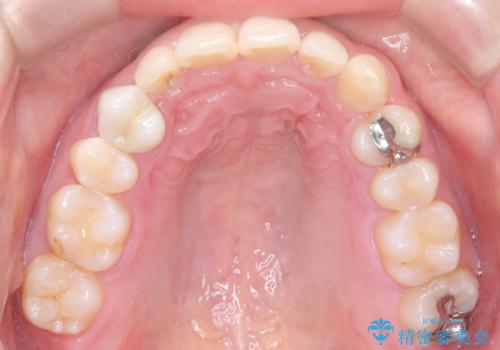

- 下の歯のがたつき(叢生)、真ん中(正中)が右にずれていることを主訴に来院されました。右上前から3番目の永久歯が埋まっている(埋伏)していることから正中は可能な限り合わせることをゴールとしてマウスピースでの矯正治療を選択しました。

今回の矯正治療では、透明なマウスピース型の装置インビザラインを使用しました。がたつきをとるため、安全性が確保できる範囲で歯と歯の間を少し削り必要なスペースを確保しました。